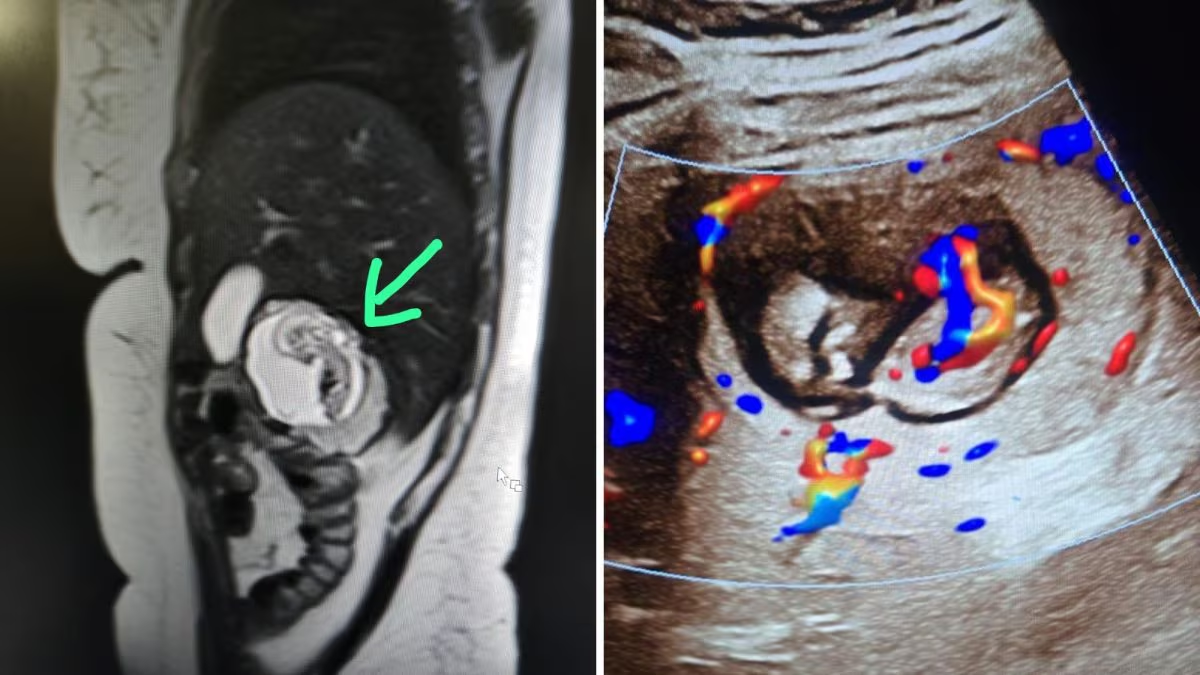

உத்தரப்பிரதேச மாநிலம் புலந்த்சாகரில் நடந்த ஒரு அசாதாரண மருத்துவ சம்பவம், மருத்துவ உலகையே வியப்பில் ஆழ்த்தியுள்ளது. 30 வயது பெண் ஒருவருக்கு எடுக்கப்பட்ட எம்.ஆர்.ஐ. ஸ்கேனில், அவர் 12 வார கர்ப்பமாக இருப்பதும், ஆனால் கரு, கருப்பையில் இல்லாமல், கல்லீரலில் வளர்ந்து வருவதும் கண்டுபிடிக்கப்பட்டுள்ளது.

இந்த அரிய மற்றும் ஆபத்தான நிலை இன்ட்ராஹெபாடிக் எக்டோபிக் கர்ப்பம் (Intrahepatic ectopic pregnancy) என்று அழைக்கப்படுகிறது. இதில் கருவானது கல்லீரல் திசுக்களுக்குள் பதிந்து வளர தொடங்குகிறது. இந்தியாவில் இதுவரை இப்படி ஒரு சம்பவம் பதிவானதில்லை என்பதால், இதுவே நாட்டின் முதல் கேஸ் என நிபுணர்கள் கருதுகின்றனர்.